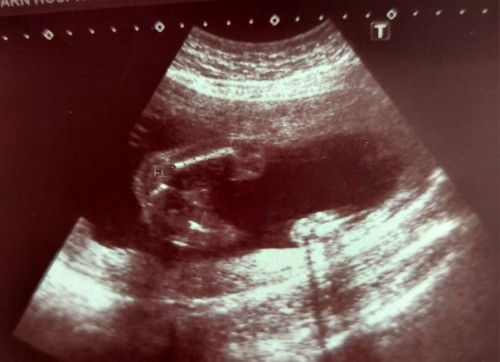

ท้อง20wแต่ในใบซาวด์21wค่ะ รบกวนแม่ๆช่วยดูทีนะคะว่าน้องเพศอะไร หมอบอกคิดว่าเป็นชายแต่ไม่คอนเฟิร์มค่ะต้องรออีก10wถึงจะชัด

เหมือนผู้ชายเลยค่ะ